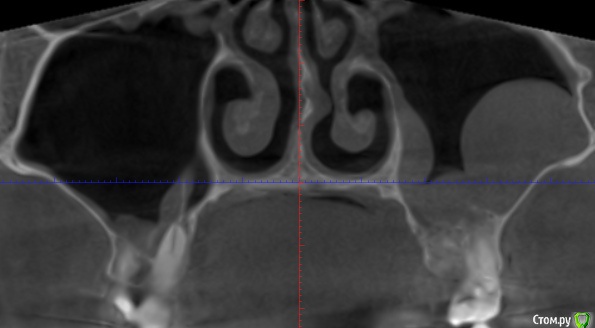

klemento Опубликовано 29 октября, 2019 Автор Поделиться Опубликовано 29 октября, 2019 (изменено) Я же просил сделать вас снимок на визиографе, эта томограмма читабельна, лечите каналы 7ого, 4,6 каналы лечить не нужно,4,6,7 затем протезировать, 5й похоже на выход, очень похоже на перфорацию или трещину, в пазухе явления из-за воспаления вокруг корней 7ого. скаться в Минск из Гомеля не такая уж и непосильная проблема....И снова здравствуйте. Был на консультации в "лучшей клинике" города. Их заключение - удалить 26,27. На 2.6 показали воспаление которое мол в пазухе уже (снимок прилагаю). И типа эти зубы страшно оставлять т.к. гайморит(синусит). В 2.5 никаких проблем не увидели. После удаления смотреть за пазухой и при хорошем исходе синуслифтинг и имплантация... Обращался в несколько клиник Минска удалённо - 27 - на выход, 26 и 25 кто-то видит проблемы, кто-то нет.Я в заблуждении, если бы не Ваше сообщение уже бы давно удалил зубы. Искать дальше клинику?Постоянная ссылка на КТ если что: https://drive.google.com/open?id=1f2ptFqgFpPtr9B8FsYOVlTv_BBs7ex2j Изменено 30 октября, 2019 пользователем klemento Ссылка на комментарий

krokomot Опубликовано 30 октября, 2019 Поделиться Опубликовано 30 октября, 2019 Дело ваше, я свое мнение уже высказал, а снимок на визиографе вы так и не предоставили...ищите эндодонтиста, тот который занимается лечением каналов профессионально. Ссылка на комментарий

klemento Опубликовано 30 октября, 2019 Автор Поделиться Опубликовано 30 октября, 2019 (изменено) Дело ваше, я свое мнение уже высказал, а снимок на визиографе вы так и не предоставили...ищите эндодонтиста, тот который занимается лечением каналов профессионально.Про снимок твердят не имеет смысла. 26 на снимках в прошлом сообщении, где пятна - это не гранулема/киста/воспаление?Нашел старые за август. Не знаю информативны или нет. На первом 26 и 25. На втором 27 и 26. Изменено 30 октября, 2019 пользователем klemento Ссылка на комментарий

krokomot Опубликовано 30 октября, 2019 Поделиться Опубликовано 30 октября, 2019 Вы тогда определитесь кому больше доверяете. Я смотрю 5-6 новых томограмм ежедневно с разными ситуациями, сложными и простыми, а у вас 1 томограф на весь Гомель, опыта работы с томограммами у докторов очень мало, все мои пациенты проходят томографическое исследование, при необходимости я делаю снимки на визиографе, когда это требуется, в вашем случае требуеся. По 10 раз я не буду объяснять, что нужно у меня нет на это времени. Ссылка на комментарий